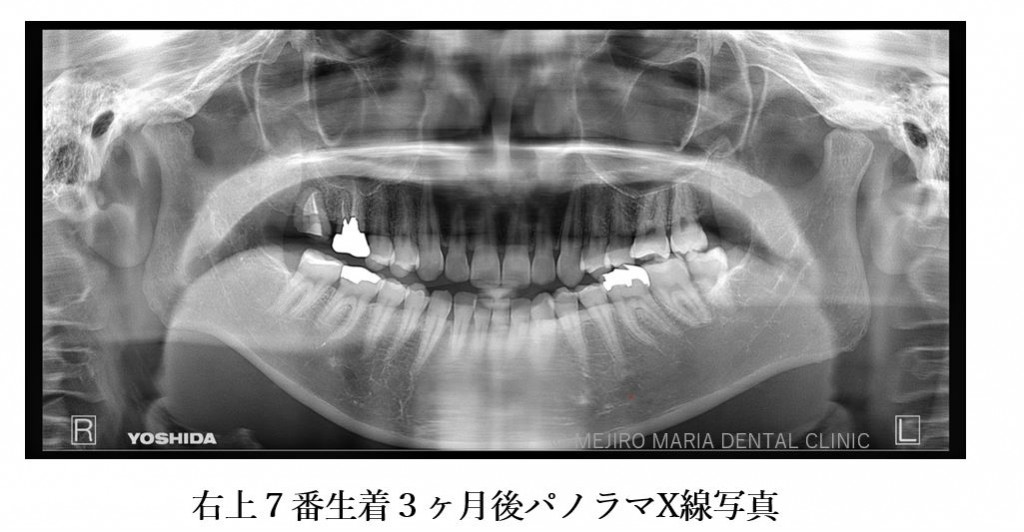

目白マリア歯科 親知らずの移植でインプラントを回避した症例_根生着後3ヶ月パノラマX線画像

精密根管治療終了後3ヶ月で、術前に確認できた病変の縮小は顕著に確認でき、予後経過は良好と判断します。今後、最終補綴処置に移行し経過観察を行っていきます。

手術後、2週間で移植歯の生着を確認し、通法通りの精密根管治療を施したことで、根尖周囲組織に確認できた病変も3ヶ月後の経過観察では縮小を確認しました。